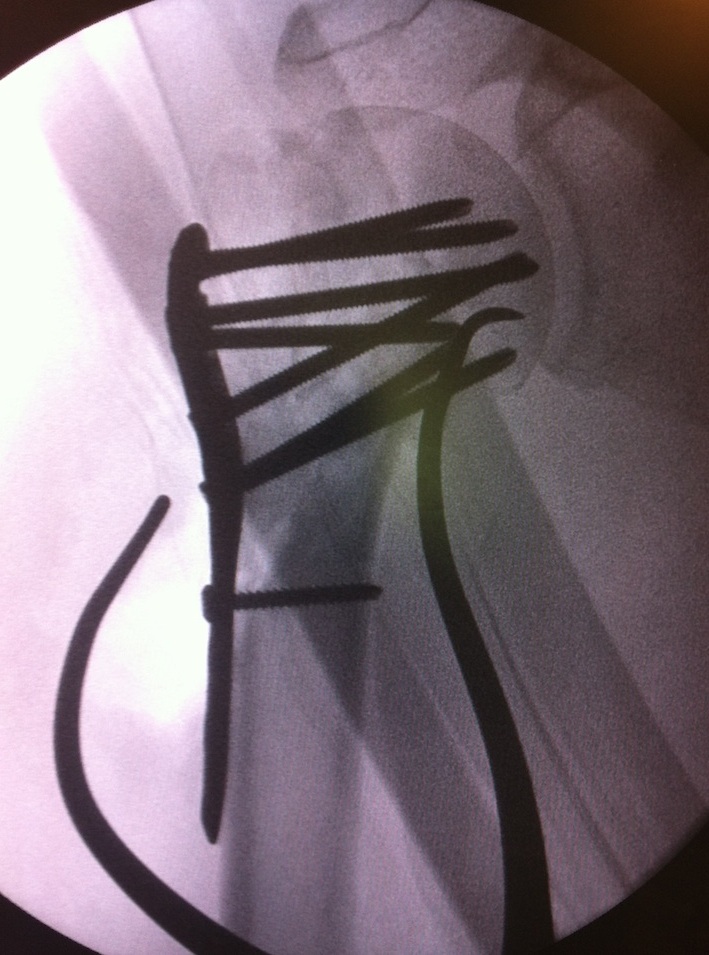

proximal humerus fracture Background ORIF with locking plate Arthroplasty Greater tuberosity fractures Lesser tuberosity fractures / avulsions Book traversal links for Proximal humerus fractures ‹ Pectoralis Major Tears Up Background ›